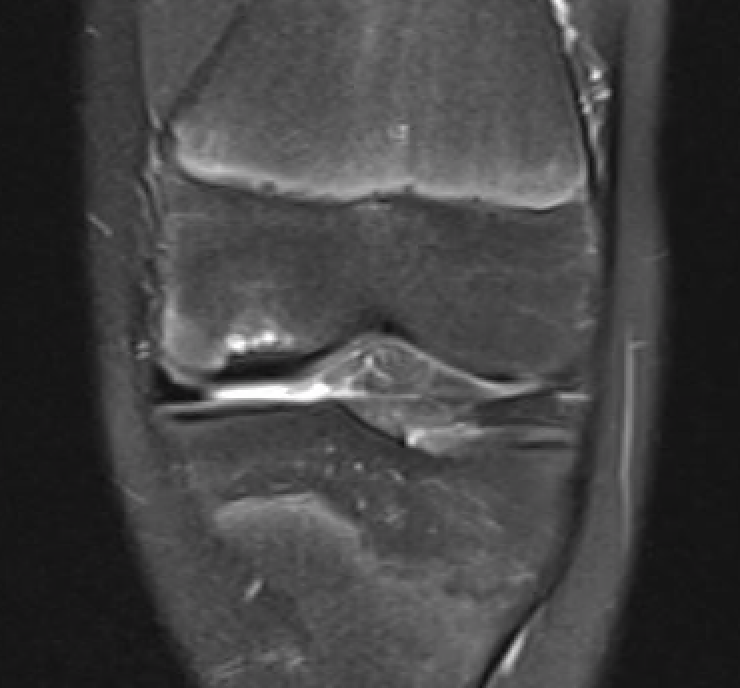

T1 sagittal on presentation T1 sagittal six months later

Progression of reossification over 6 months following drilling